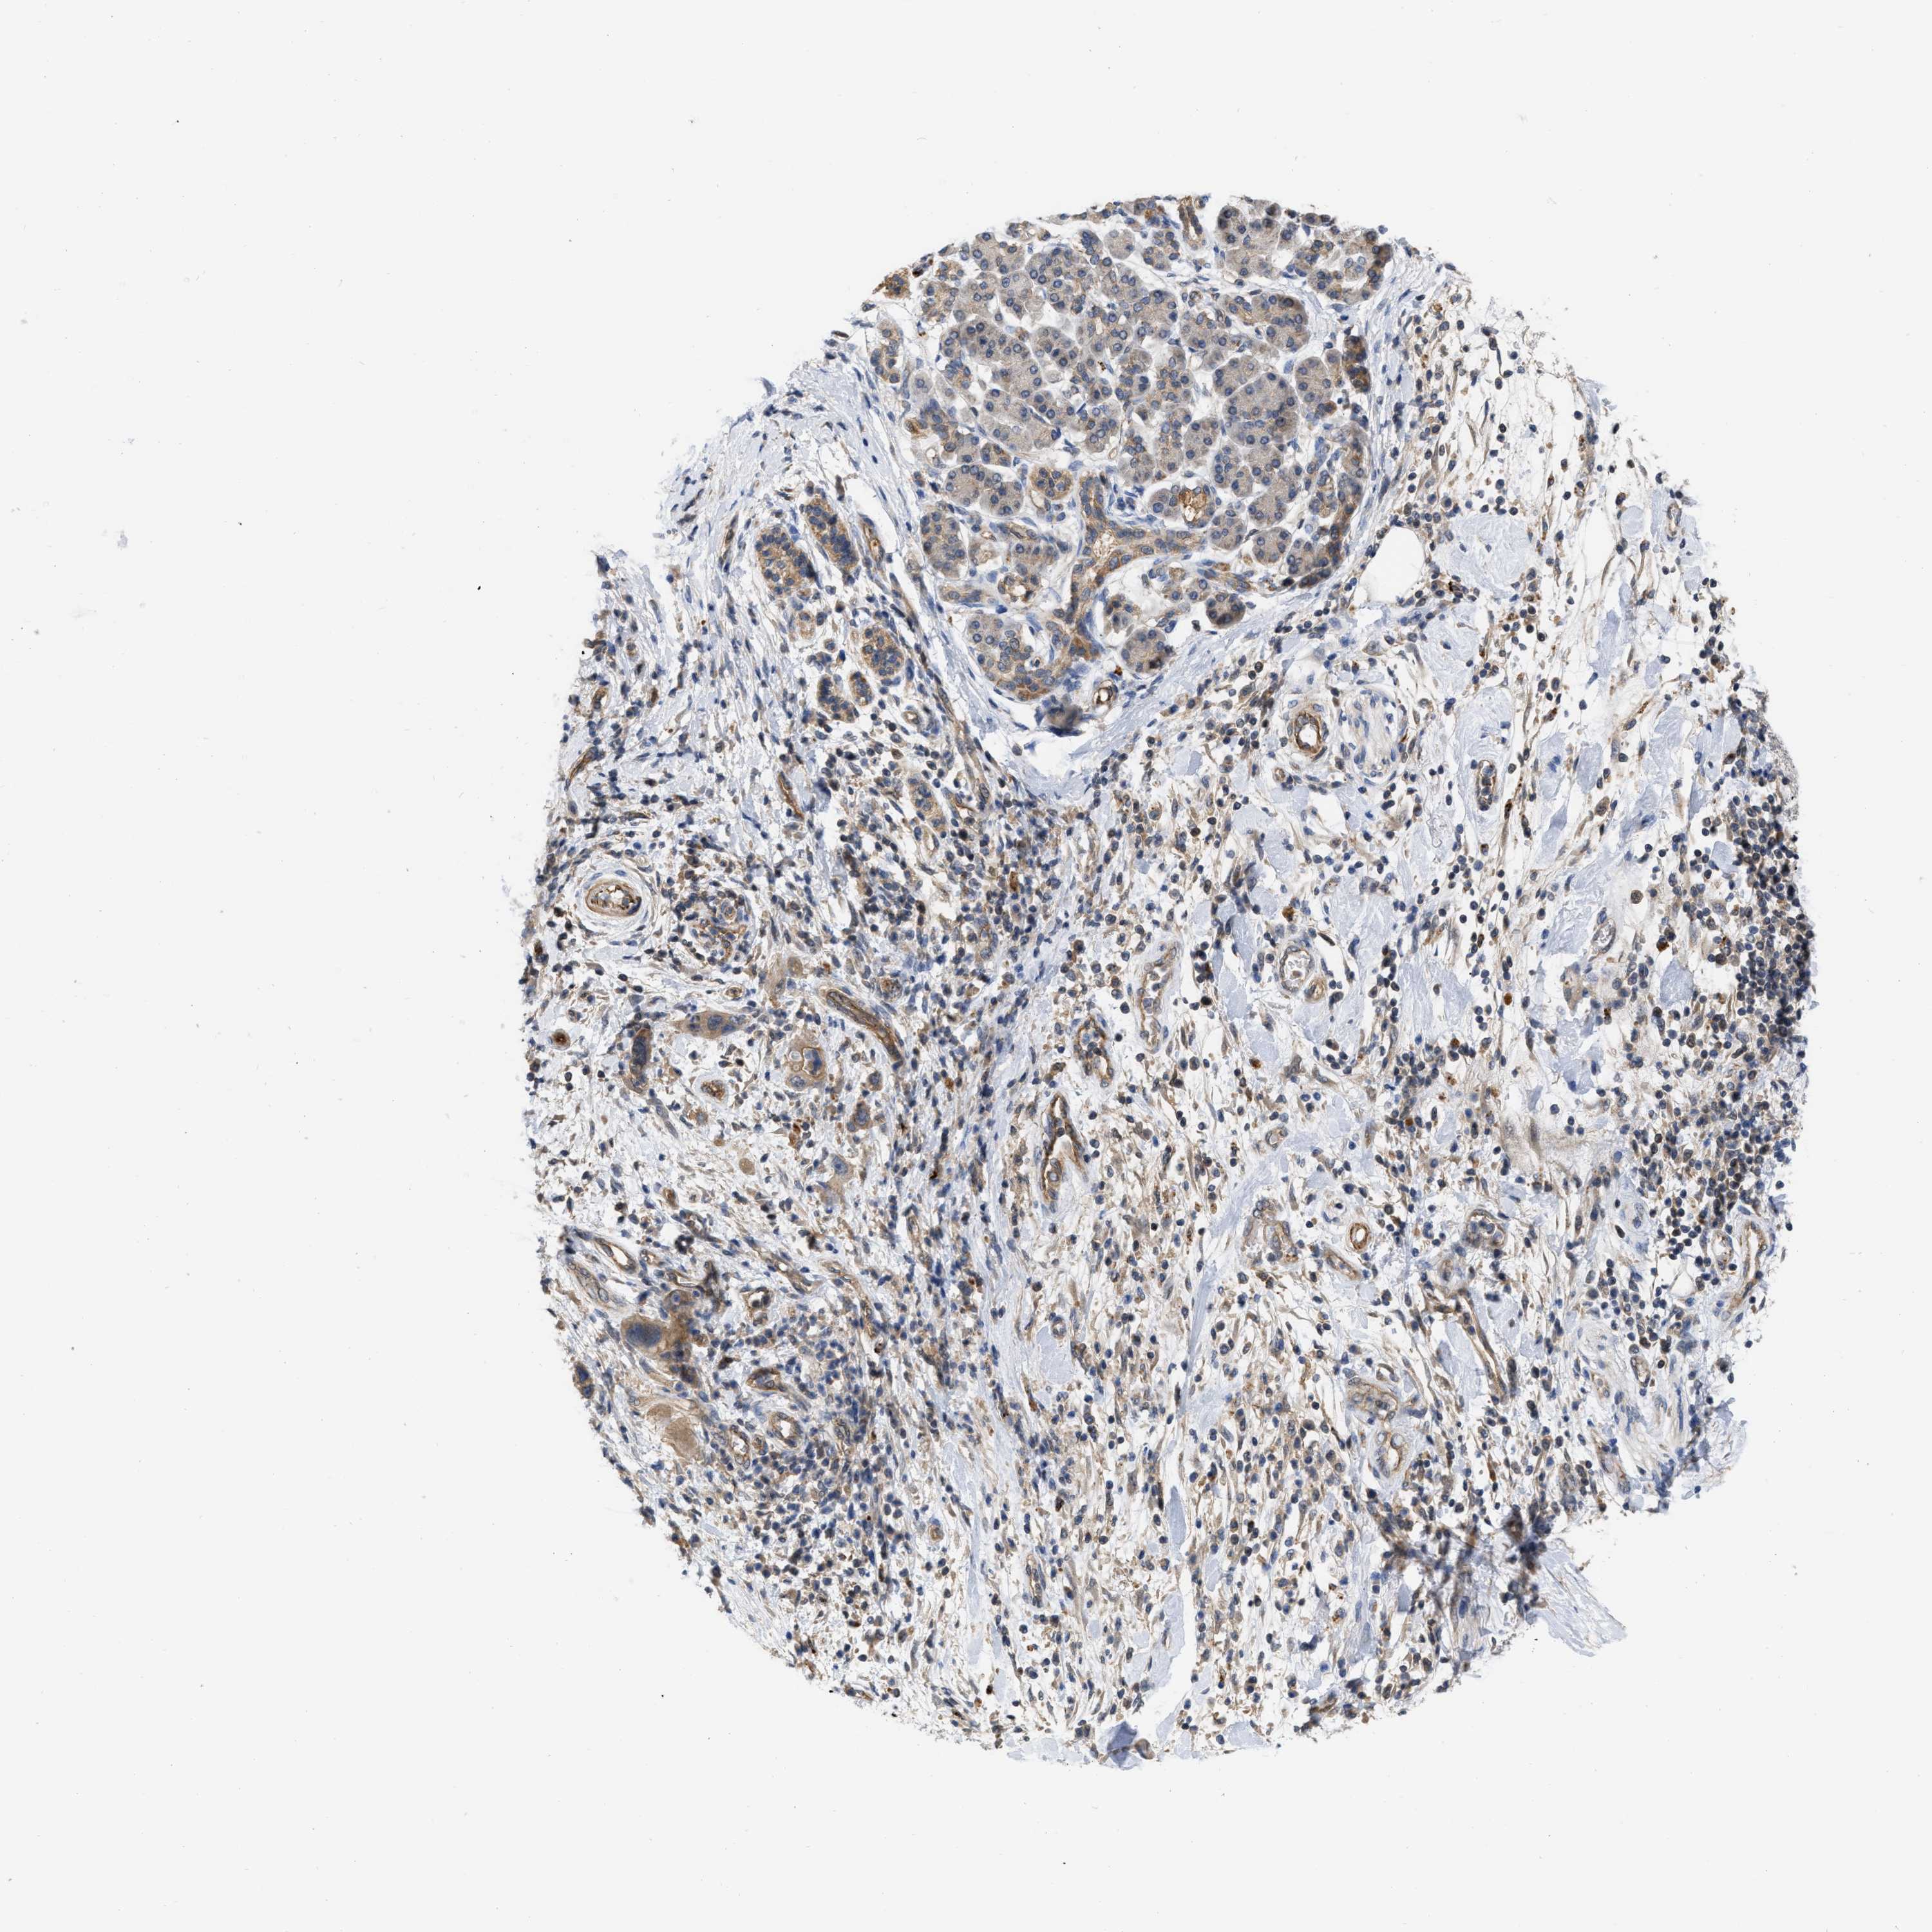

PANCREATIC CANCER - Protein expressioni

A mouse-over function shows sample information and annotation data. Click on an image to view it in a full screen mode. Samples can be filtered based on level of antibody staining by selecting one or several of the following categories: high, medium, low and not detected. The assay and annotation is described here.

Note that samples used for immunohistochemistry by the Human Protein Atlas do not correspond to samples in the TCGA dataset.

Antibody stainingi

Antibody staining in the annotated cell types in the current human tissue is reported as not detected, low, medium, or high, based on conventional immunohistochemistry profiling in selected tissues. This score is based on the combination of the staining intensity and fraction of stained cells.

Each image is clickable and will lead to virtual microscopy that enables deeper exploration of all samples and also displays staining intensity scores, fraction scores and subcellular localization as well as patient and tissue information for each sample.

Antibody HPA019832

Antibody HPA024338

Staining

High

Medium

Low

Not detected

Intensity

Strong

Moderate

Weak

Negative

Quantity

>75%

75%-25%

<25%

None

Location

Nuclear

Cytoplasmic/membranous

Cytoplasmic/membranous,nuclear

Adenocarcinoma, NOS